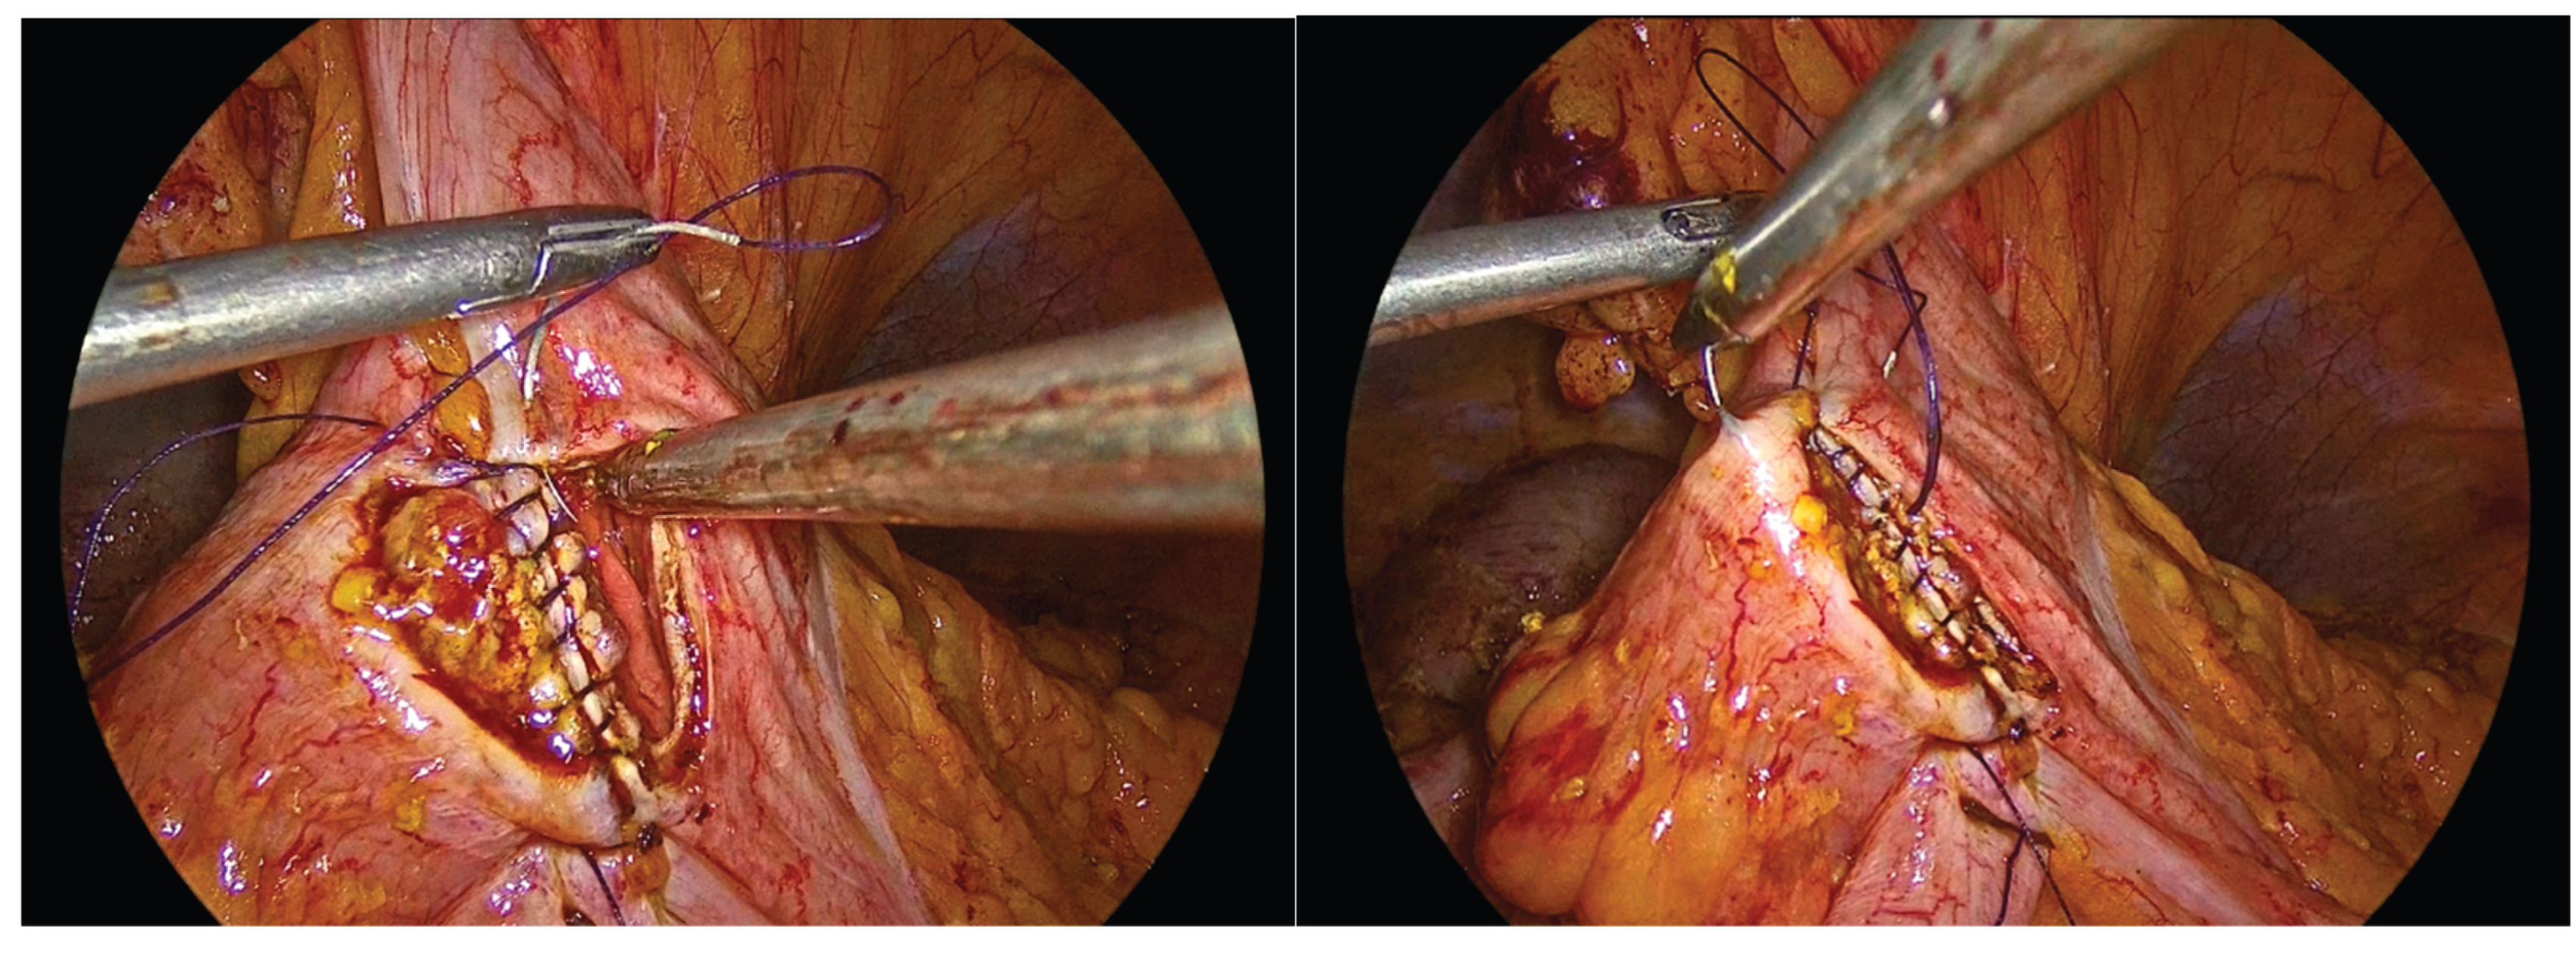

The inner layer of the anastomosis is constructed using a continuous full-thickness absorbable 3-0 Vicryl Plus suture, initiated proximally to the surgeon. Suturing proceeds from the proximal aspect toward the antimesenteric border, incorporating all the layers of the bowel lumen, with bites placed at intervals of 0,5 to 1 cm. Upon reaching the distal end of the enterotomy, the suture is continued along the opposite side, and the anterior layer of the anastomosis is completed after reaching back the proximal initial part of the anastomosis and tying the suture and to the initial knot.

Figure 8. First suture of the anastomosis, using an absorbable 3-0 Vicryl Plus suture.

Preprints 195043 g008

Figure 9. The inner layer of the anastomosis.

Preprints 195043 g009

Figure 10. Completion of the inner full-thickness layer of the anastomosis and transition to construction of the anterior layer.

Preprints 195043 g010

Figure 11. Anterior outer layer of the anastomosis.

Preprints 195043 g011

Figure 12. The completed single-layer handsewn intracorporeal anastomosis.

In order to facilitate the ease of the construction of this anastomosis, we use right-hand, left-hand, back-hand, and fore-hand techniques. We take care not to evert the mucosa of the colon or ileum, but on the contrary to invert both mucosa into the suture line. We also try to be precise with the sutures and as far as possible the anastomosis to be symmetric. Completion of the anastomosis is followed by meticulous inspection of the suture line and stapled bowel ends to ensure adequate hemostasis and the absence of hematoma formation.